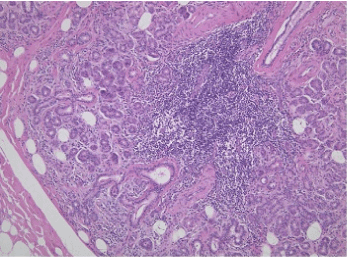

A 54-year-old Japanese male was referred to our clinic with a chief complaint of swelling and pain in the right submandibular region. He had experienced the swelling in 1995 but he left it untouched because there were no severe symptoms. He noticed an increase in the swelling and pain, and thus he was referred to our clinic in October 2018. According to his history, the patient was under treatment for hypertension. His blood pressure was 120/96 mmHg, and he was diagnosed with old myocardial infarction and atrioventricular block leading to bradycardia on the basis of an electrical cardiograph; however, neither of these conditions has pathological significance. A clinical examination found obvious swelling in his right submandibular area (Figure 1). The mass-like swelling was palpable and was the size of walnut. The mass had an elastic soft texture, mobility, and was painful when touched. Intraorally, the right mouth floor mucosa was reddened, mildly swollen, and tender. Yellow-white viscous liquid spilled out from the sublingual salivary papilla. A panoramic X-ray examination revealed a curved, elliptical radiopaque mass in the right submandibular salivary gland region (Figure 2A). Evaluation of the bone window on Computed tomography (CT) revealed a hard tissue about 30 × 20 mm in size located in the gland body (Figure 2B). No neurological disturbance of the facial, lingual, or sublingual nerve was evident. Based on the examinations, a clinical diagnosis of right submandibular sialolithiasis resulting in submandibular sialadenitis was made. To reduce inflammation, amoxicillin 750 mg/day was orally administered for 4 days. In December 2018, the patient underwent surgical extraction of the submandibular salivary gland under general anesthesia after the inflammation was reduced. Figure 3 shows the facets of the submandibular gland and the internal calculi. The calculi were flexed in line with the mylohyoid muscle, and the surface was rough and grayish-yellow in color. Figure 4 shows the hematoxylin-eosin staining of the extracted submandibular gland, and the main composition of the region was inflammatory saliva tissue. Mild-to-severe migration of lymphocytes and plasmacytes, which are chronic inflammatory cells, was observed around the salivary tissue. Some salivary tissue degenerated into adipo-tissue. Acinic cells had atrophied, and the saliva duct was extended as a result of migration of the inflammatory cells. The pathological diagnosis was chronic sialadentitis and sialolithiasis. The calculi were analyzed using energy dispersive x-ray fluorescence (EDX-7000, Shimadzu, Tokyo, Japan) (Figures 1-3). The main components of the sialolithiasis were Ca: 78.6%, P: 21%, S: 0.25%, Fe: 0.07%, and Cu: 0.04% (Figure 5). The patient has remained in good condition since the surgery.

Figure 4. Histology of the submandibular gland. The acinic cells atrophied and the saliva duct was extended as a result of the migration of inflammatory cells (×100)